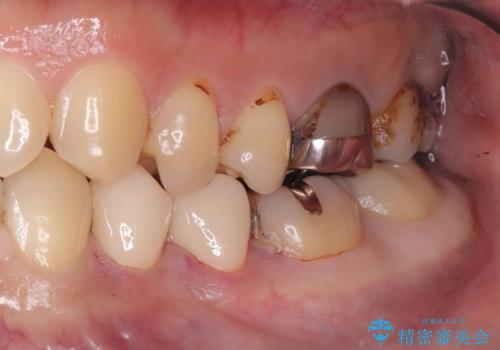

- CRが劣化し欠けてしまっている状態でした。 虫歯を除去後、歯を破折から守るためオールセラミッククラウンで治療を行いました。

オールセラミッククラウンで治療後、お痛みや食べ物も詰まることなく経過は良好です。